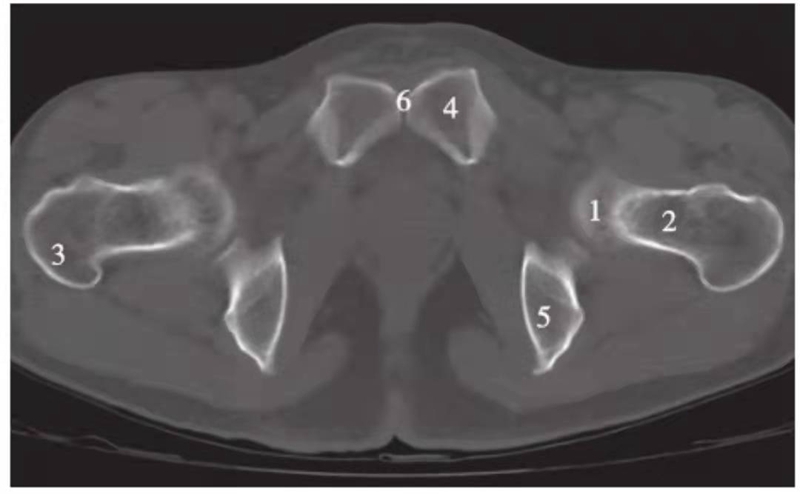

横轴位

图1 正常股骨头顶部层面(骨窗)

1.股骨头;2.耻骨;3.坐骨;4.髋臼窝;5.髋臼前唇;6.髋臼后唇